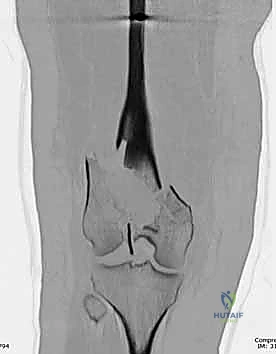

- الأشعة السينية (X-Rays): أخذ صور من زوايا متعددة (أمامي خلفي، وجانبي) لتحديد موقع الكسر ونوعه.

- الأشعة المقطعية (CT Scan): وهي ضرورية جداً في كسور عظم الفخذ البعيدة، خاصة إذا كان الكسر يمتد إلى داخل مفصل الركبة (Intra-articular fractures). تساعد الأشعة المقطعية الدكتور هطيف على بناء نموذج ثلاثي الأبعاد للكسر، مما يسهل التخطيط الجراحي وتحديد أماكن وضع المسامير بدقة.

المرحلة الثالثة: إرجاع العظم (Reduction)

هذه هي الخطوة الأكثر أهمية. يقوم الدكتور هطيف بإعادة القطع العظمية المكسورة إلى مكانها التشريحي الأصلي. إذا كان الكسر ممتداً داخل المفصل، يتم تثبيت السطح المفصلي أولاً باستخدام مسامير دقيقة لضمان سطح أملس يمنع الاحتكاك والخشونة مستقبلاً.